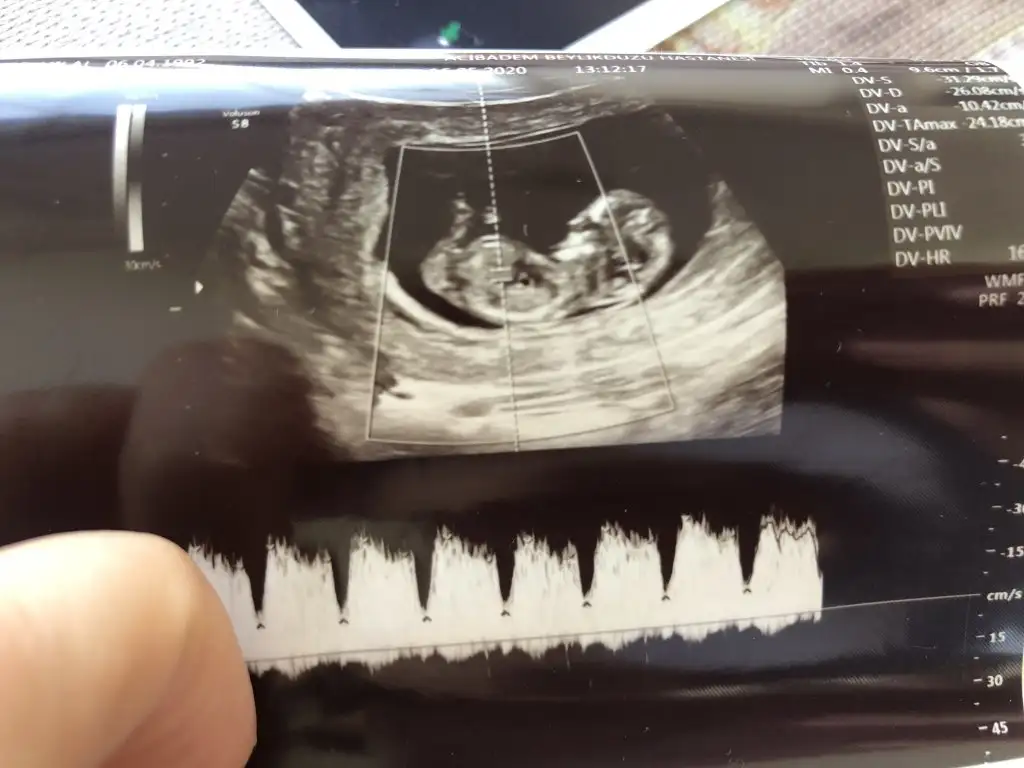

Merhaba ilki 9 haftalık son üçü 11 haftalık bir tahminde bulunabilir misiniz:)